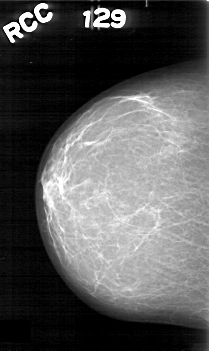

Digital Database for Screening Mammography

Volume: benign_09 Case: D-4045-1

D_4045_1.RIGHT_CC

RIGHT_CC LINES 5251 PIXELS_PER_LINE 3121 BITS_PER_PIXEL 12 RESOLUTION 43.5 NON_OVERLAY